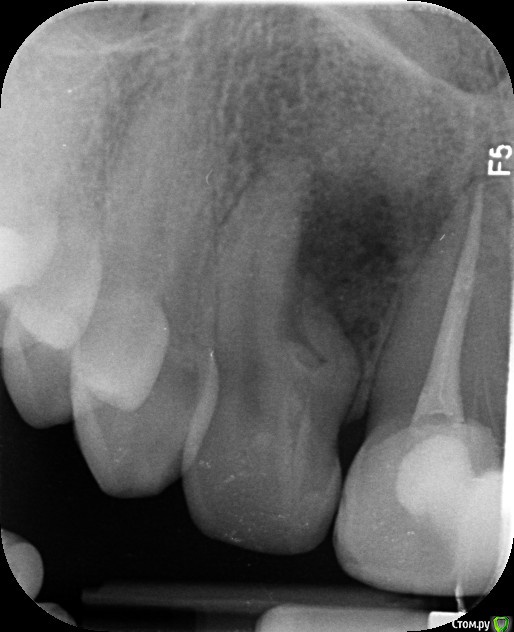

olga1985 Опубликовано 16 августа, 2016 Автор Поделиться Опубликовано 16 августа, 2016 последний ренген прикрепляю. заранее спасибо за ответ! Ссылка на комментарий

shishok Опубликовано 16 августа, 2016 Поделиться Опубликовано 16 августа, 2016 А каналы в аномальном зубе Вам не лечили?В 11 зубе возможно не трещина,а пропакованная латераль. Ссылка на комментарий

olga1985 Опубликовано 16 августа, 2016 Автор Поделиться Опубликовано 16 августа, 2016 Каналы не лечили, врач решил что это не киста, так как между зубов. Сходила к другому врачу, ещё раз сделала снимок: трещины нет, это какой-то глюк с первым рентгеном. Последний врач прописал два антибиотика, сказал если будет усиливаться отек то вырывать зуб сразу. Отправил домой на неделю и через неделю прийти к нему пломбировать каналы. Сказал, что если это не поможет, то снова резать и отрезать часть корня. Сказал, что он в сильных сомнениях насчёт зуба. Он наверняка мертвые после абсцесса который случился. Я опять не понимаю: простое пломбирование каналов же не поможет? Ссылка на комментарий

DmitrySH Опубликовано 16 августа, 2016 Поделиться Опубликовано 16 августа, 2016 У этой "кривульки" так просто их не получится запломбировать. Один да, а остальное под вопросом Ссылка на комментарий